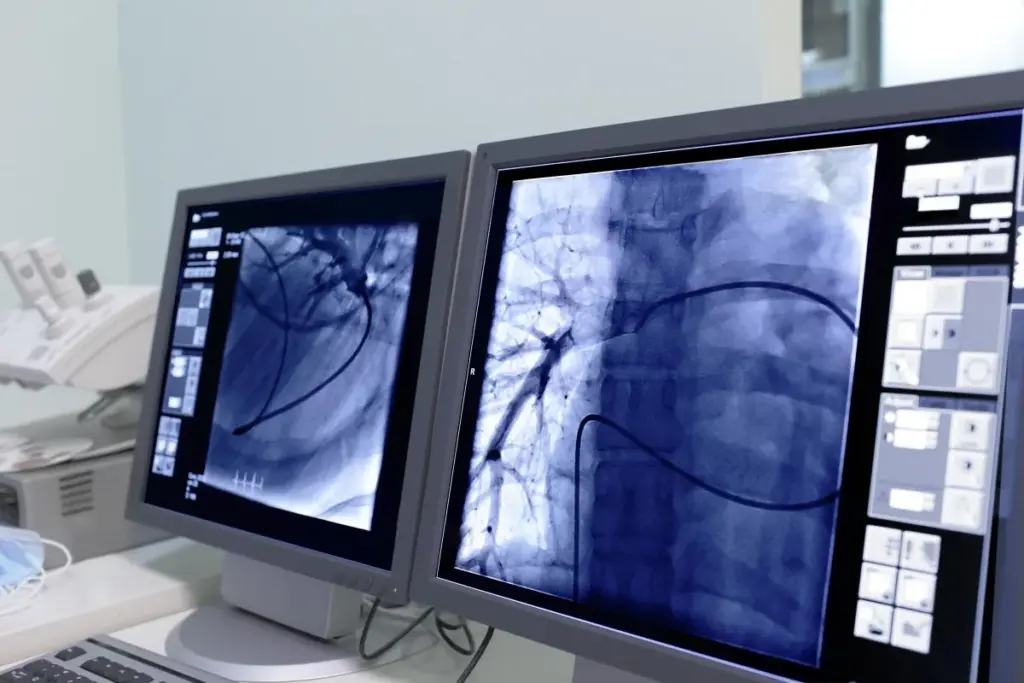

IR covers a wide range of procedures. These include angiography, embolization, and tumor ablation. We use X-ray, ultrasound, and MRI to guide these treatments.

These treatments are done under image guidance. This ensures precision and reduces risks. Real-time imaging helps us navigate complex anatomy accurately.

Image-Guided Precision in Treatment

IR’s main advantage is its image-guided precision. Advanced imaging technologies allow us to:

- Enhance Accuracy: Real-time imaging helps us target treatment areas precisely.

- Reduce Complications: Minimally invasive procedures have fewer complications than open surgery.

- Improve Recovery Times: Patients recover faster because IR procedures are less invasive.